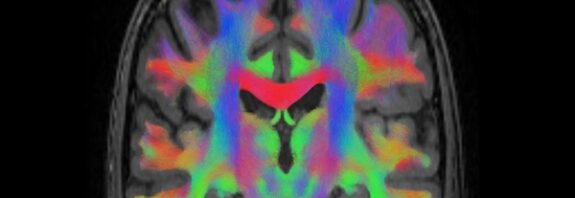

Brain Circuitry Discovered That Could Explain How Placebos Relieve Pain